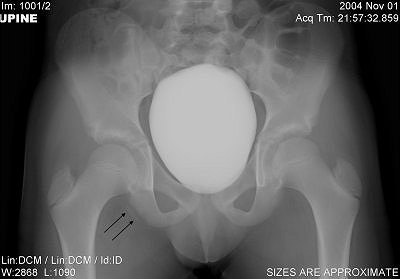

Plain radiographs, including an anteroposterior view of the pelvis, showed an avulsion of the right ischial tuberosity in the typical inferolateral location. An MR exam demonstrated osseous and soft-tissue edema, along with an avulsion fracture of the right ischial tuberosity (Figures 1-4).

| Figure 1. Anteroposterior conventional radiograph of the pelvis demonstrates an avulsion of a fragment of the inferolateral portion of the right ischial tuberosity (black arrows). |